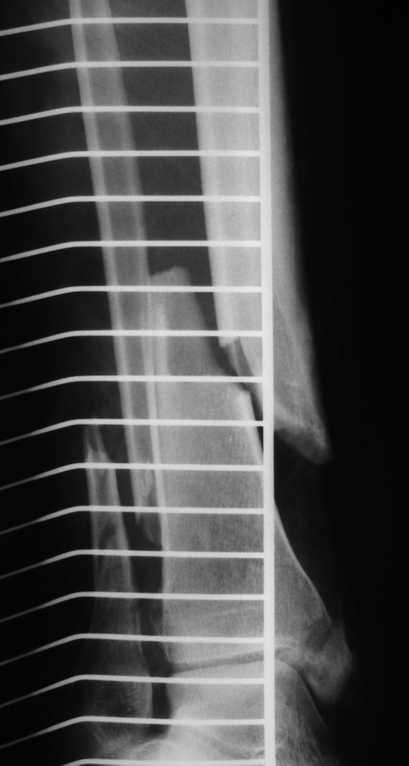

48 yo male, crush injury (esp. Gustilo IIIA ) of distal tibia managed nonoperatively ( cast ! ABX) for 2 days, was transferred to us.

There,s no signs of infection but condition of skin is bad ( large contusion, Tscherne 3 ) What kind of treatment: definitivly or staged ? Internal fixation (plate) or maybe nail + screws ? Ilizarov is an option... <br>

Имя     : DSC04433.JPG